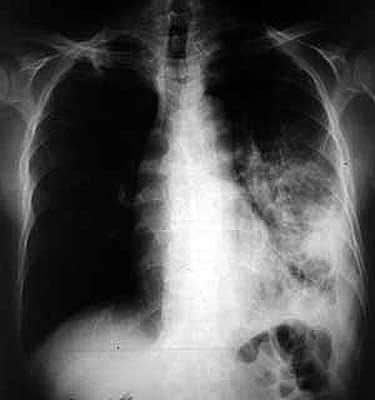

Londres, qui est la capitale ouest-européenne la plus touchée par la tuberculose, a mis en œuvre avec succès une unité mobile de dépistage par radiographie, qui se rend dans les communautés les plus à risque, selon une étude publiée dans le British Medical Journal et présentée à l’université de Warwick (centre) mercredi.

Sur les 9.040 cas de tuberculose déclarés au Royaume Uni en 2009, 38% étaient localisés à Londres (3.440 cas).

Cette ville, qui accueille de nombreux immigrés de pays pauvres, a le taux le plus important de tuberculose des capitales ouest-européennes, avec une augmentation de 30% ces dix dernières années et un doublement des cas de tuberculose multirésistante entre 2005 et 2009.

L’unité mobile a permis de dépister 16 tuberculeux par an dans ces populations vulnérables depuis 2007, et de suivre dans leur traitement plus de 100 autres personnes chaque année.